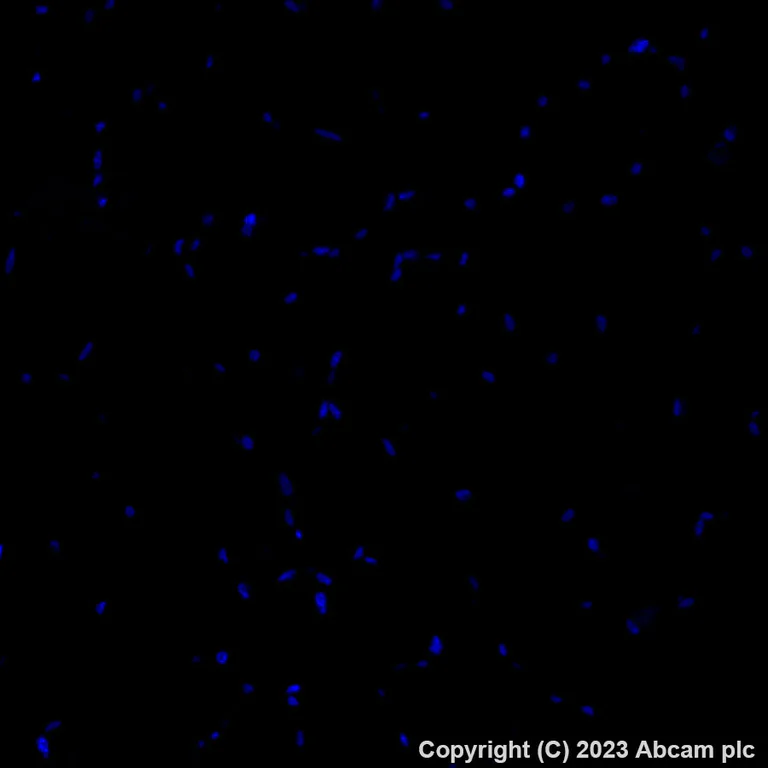

Immunohistochemistry (Formalin/PFA-fixed paraffin-embedded sections) - Alexa Fluor® 488 Anti-C Reactive Protein antibody [Y284] (AB314471)

Immunohistochemical analysis of paraffin-embedded human skeletal muscle tissue labeling C Reactive Protein with ab314471 at 1/100 (5.0 ug/ml). Negative control : no staining on human skeletal muscle. The section was incubated with ab314471 for 60 mins at room temperature (shown in green). Nuclear DNA was labeled with DAPI (shown in blue). The section was then mounted using Fluoromount®. The immunostaining was performed on a Leica Biosystems BOND RX instrument. Image was taken with a confocal microscope (Leica-Microsystems, TCS SP8). Heat mediated antigen retrieval was performed with Tris-EDTA buffer (pH 9.0, Epitope Retrieval Solution2) for 40 mins.